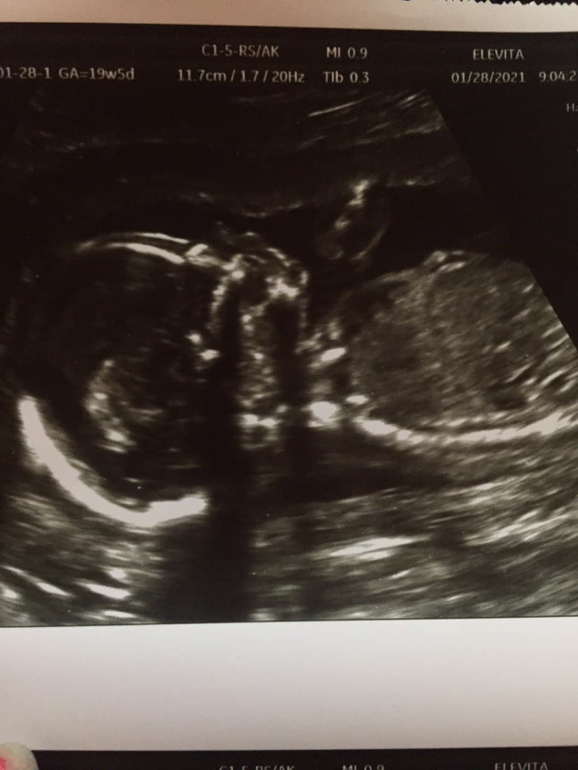

На 2 фото если это ножки и вид снизу, то точно девочка. Там три полоски одна под другой, так у девочек на узи половые органы выглядят)

На девочку похоже. Была такая картинка, что у мальчика под углом 45 градусов бугорок будет, а у девочки прямо